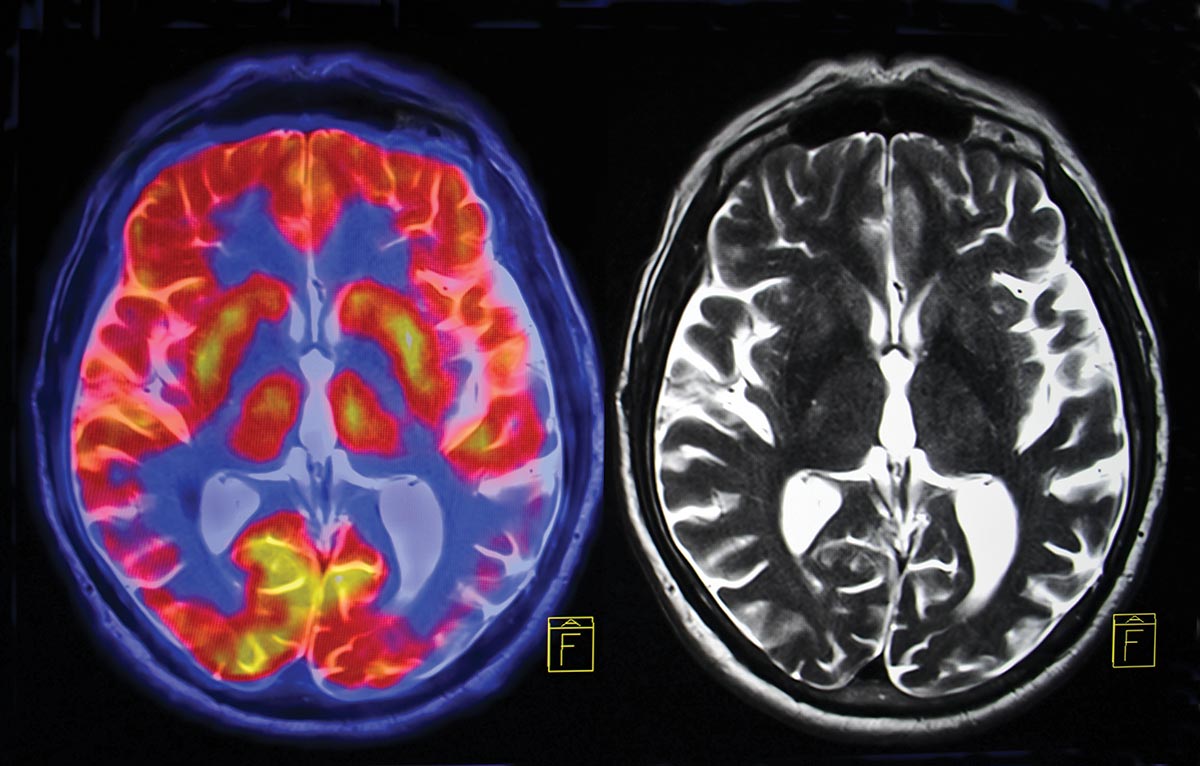

Image Credit: Jonathan Cohen.